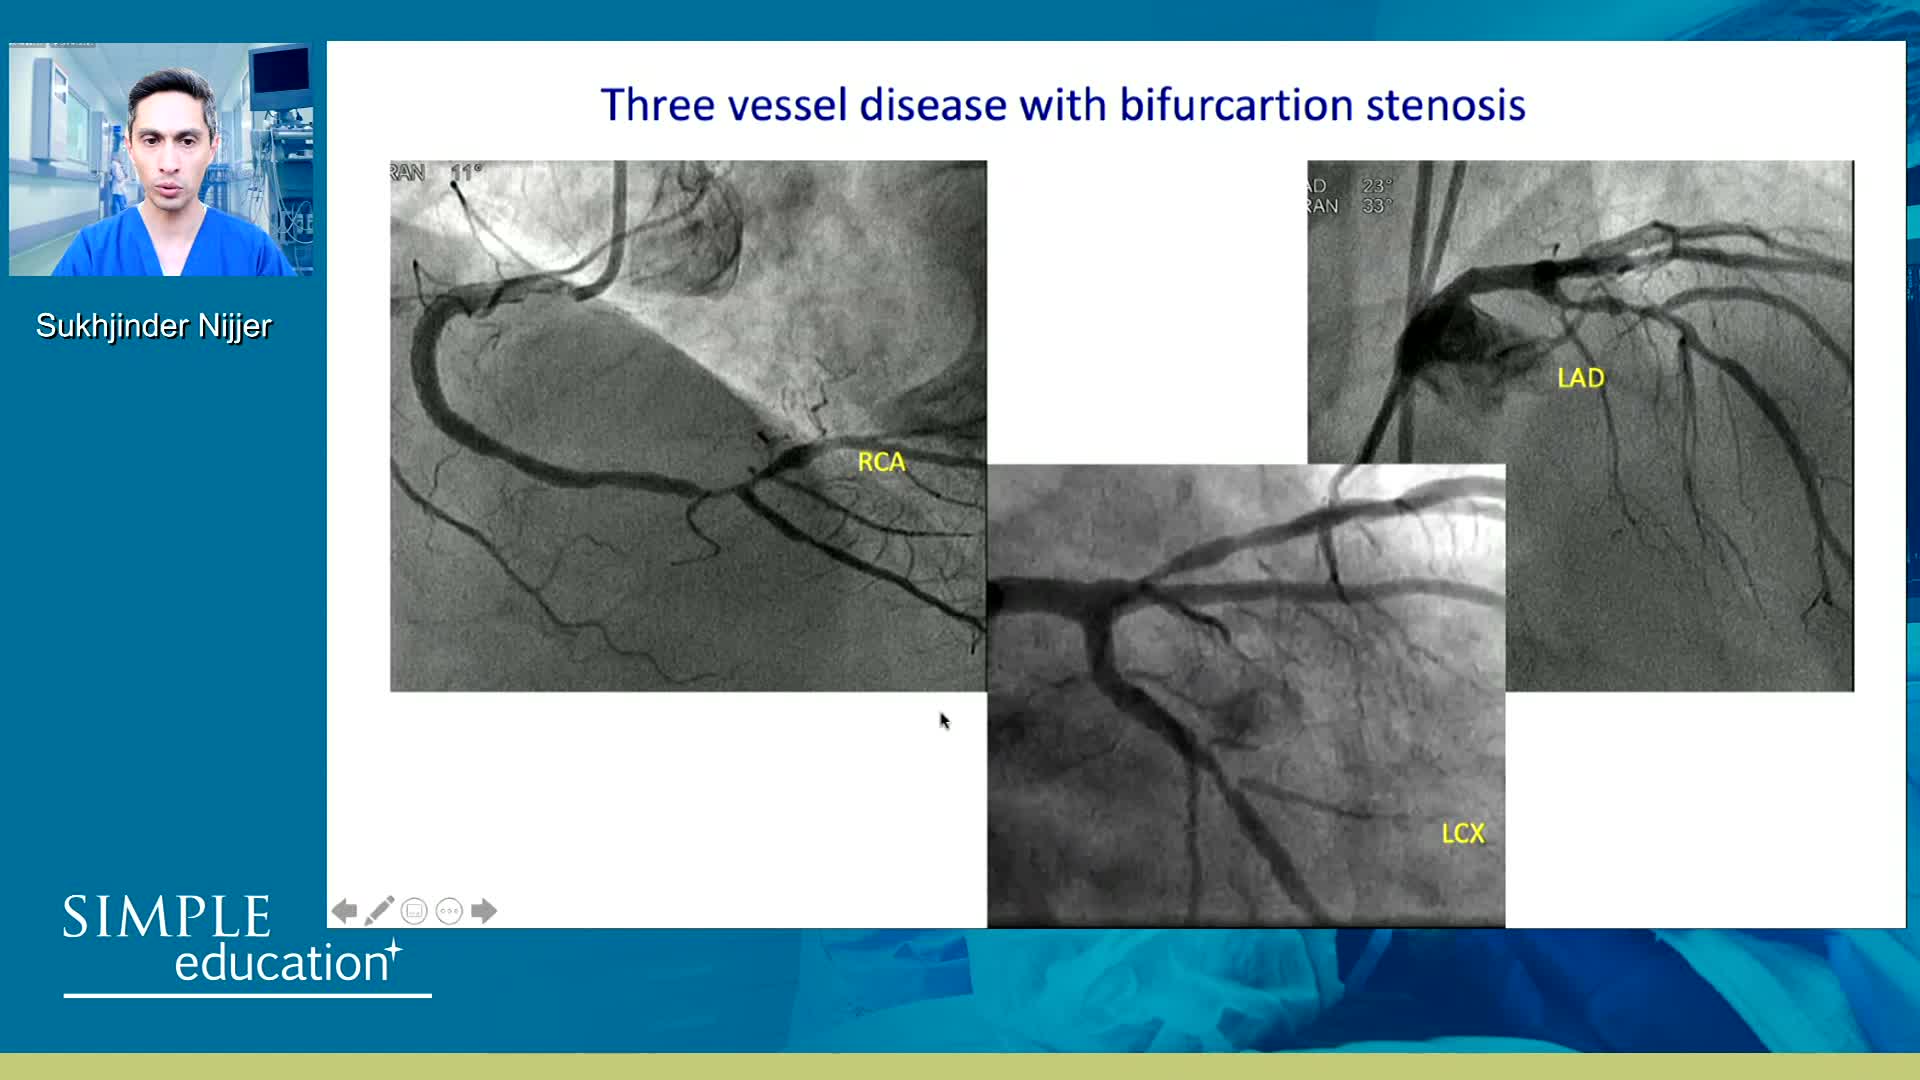

Coronary Bifurcations: An Update on Diagnosis, PCI planning and Imaging and PhysiologyGuidance - Dr Dejan Milasinovic